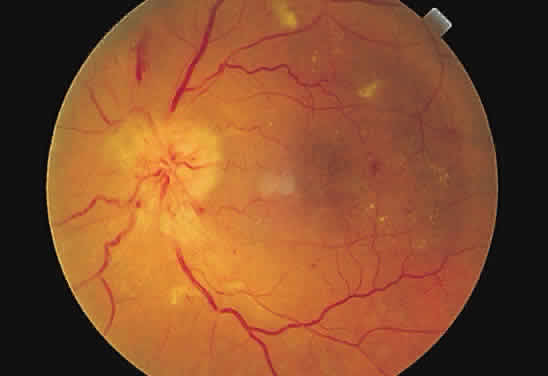

Cotton-wool spots are observed mainly in the posterior pole of the retina (Fig.23) The reason for this geographic restriction is not clear. Occlusion of

the most superficial radially oriented peripapillary capillaries (confined

in distribution to the posterior pole) has been implicated in the

pathogenesis of cotton-wool spots.9 It is also possible that nerve fiber infarcts in the periphery are not

visualized because there is insufficient inspissated axoplasmic material

in this location.  Fig. 23. Multiple cotton-wool spots along with retinal hemorrhages in a superior

temporal branch retinal vein occlusion. Fig. 23. Multiple cotton-wool spots along with retinal hemorrhages in a superior

temporal branch retinal vein occlusion.